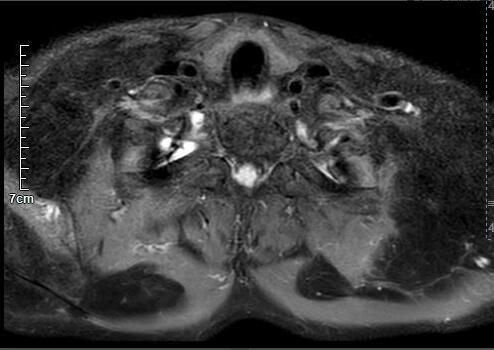

马德龙病的影像表现为颈项部等处脂肪组织蓄积增厚,可累及皮下或肌肉间隙,脂肪蓄积处没有包膜形成,蓄积脂肪内可有线状或网状纤维间隔,病变常常左右对称,颈部肌肉可受压、变细,蓄积脂肪组织内可有钙化或骨化。

李某颈部MRI